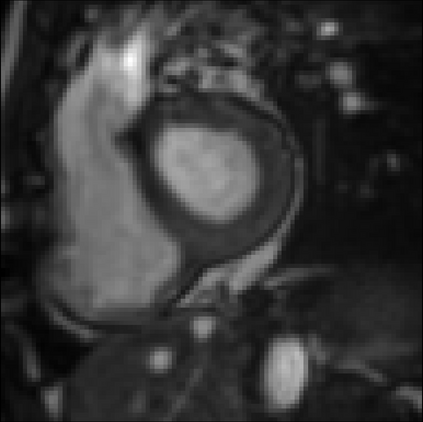

It is imperative to ensure the robustness of deep learning models in critical applications such as, healthcare. While recent advances in deep learning have improved the performance of volumetric medical image segmentation models, these models cannot be deployed for real-world applications immediately due to their vulnerability to adversarial attacks. We present a 3D frequency domain adversarial attack for volumetric medical image segmentation models and demonstrate its advantages over conventional input or voxel domain attacks. Using our proposed attack, we introduce a novel frequency domain adversarial training approach for optimizing a robust model against voxel and frequency domain attacks. Moreover, we propose frequency consistency loss to regulate our frequency domain adversarial training that achieves a better tradeoff between model's performance on clean and adversarial samples. Code is publicly available at https://github.com/asif-hanif/vafa.